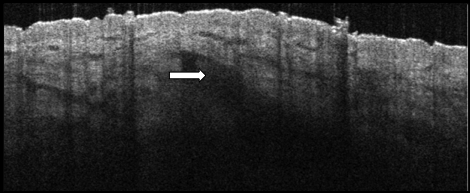

- Hyporeflective, near areflective diagonal structures tapering toward the epidermis

- Slight granular texture corresponding to the hair matrix

- The full hair bulb may not always be visible, however even at the edge of the structure it still displays a tapering at the epidermis facing side

- Hyperreflective areas can be seen in the matrix corresponding to the keratin based hair shaft